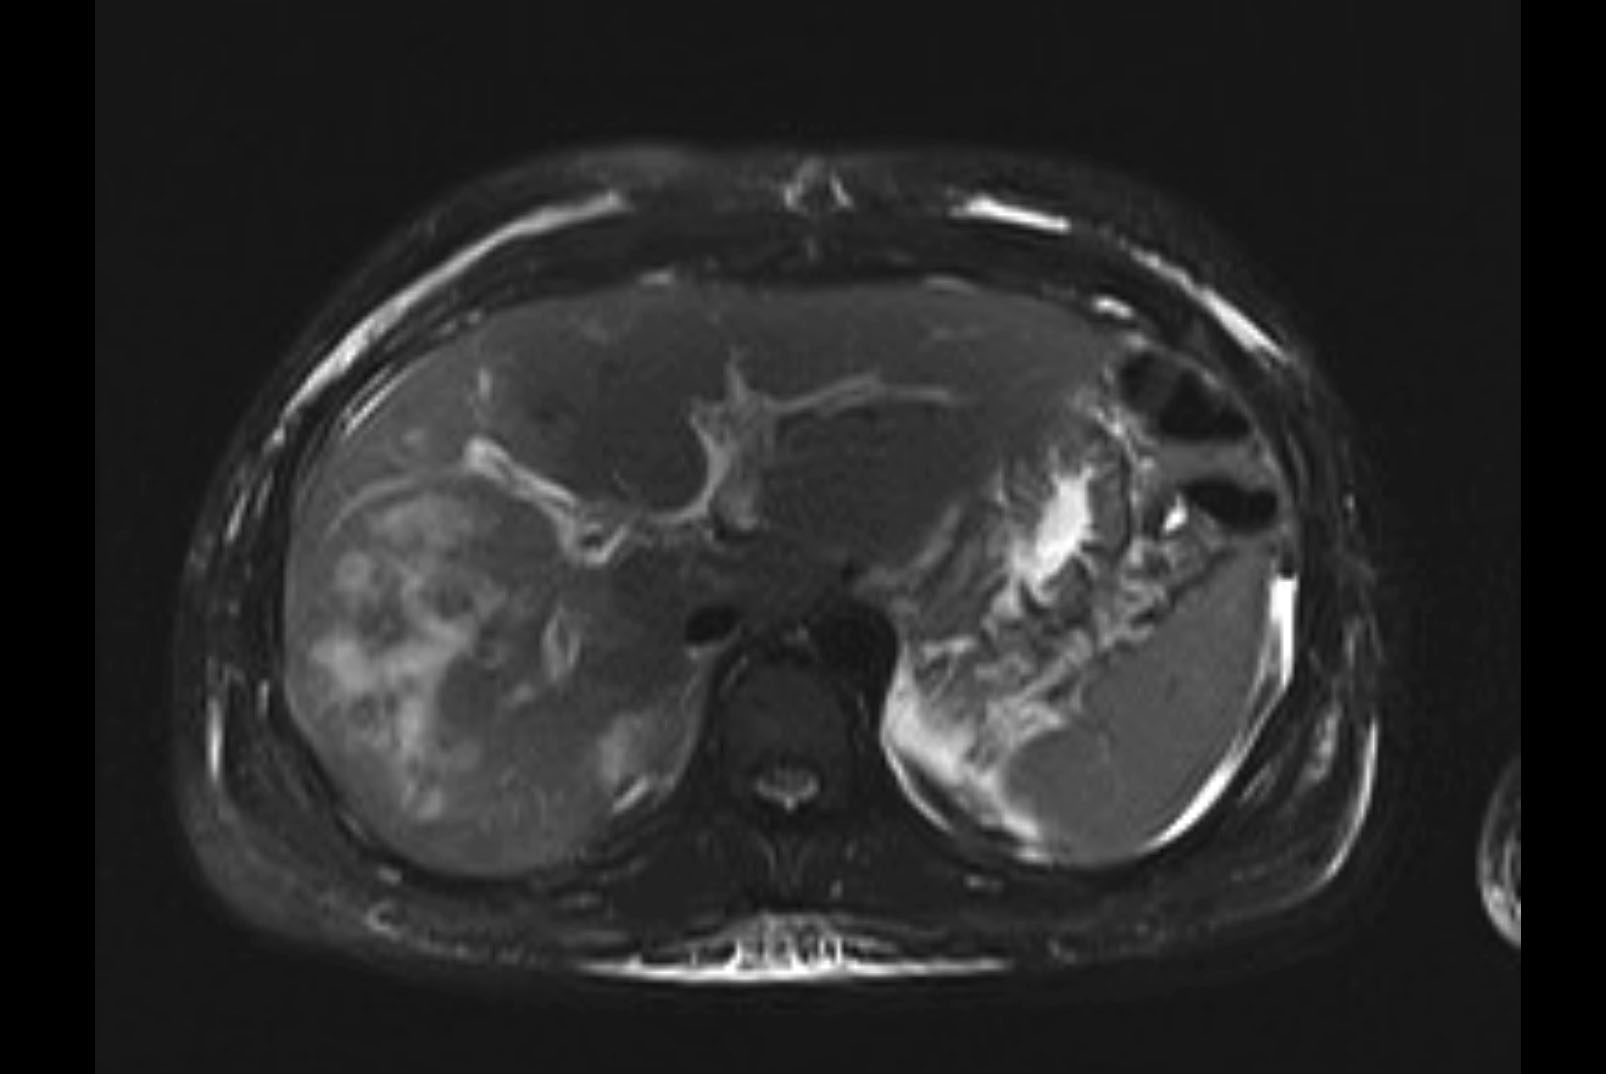

MRI T2

Imaging analysis

Based on initial findings, which issue(s) would you be most concerned about?